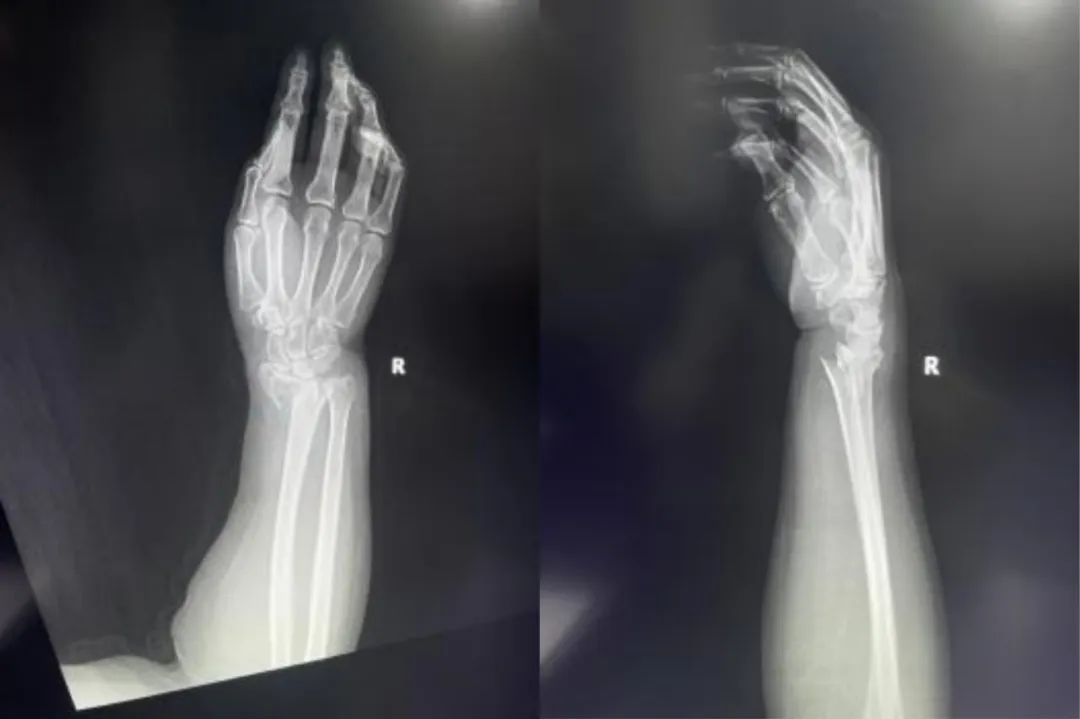

Za zaprto repozicijo zlomov s sumom na stabilnost je priporočljivo skrbno spremljanje. Pomembno je vedeti, da če niz rentgenskih žarkov po zmanjšanju kaže na nestabilnost ali premik, bo morda potrebna sprememba zdravljenja. Če je zlom potencialno nestabilen, je treba opraviti radiografijo in jo oceniti, dokler se zlom ne zaceli in stabilizira.

Stabilne zlome lahko uspešno zapremo in zdravimo z zaviranjem, sprva z opornico in kasneje s cevastim mavcem, s tedenskimi radiografijami do 3 tedne.

Če pride do pomembnih sprememb radialne dolžine, naklona dlani ali ulnarne deviacije, je treba razmisliti o kirurškem zdravljenju.